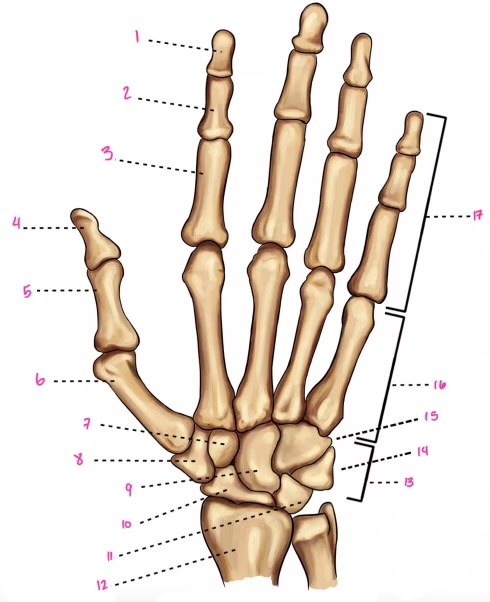

1

1

Hamate

2

New cards

2

Capitate

3

New cards

3

pisiform

4

New cards

9

Trapezoid

5

New cards

10

Trapezium

6

New cards

11

Scaphoid

7

New cards

14

Lunate

8

New cards

15

Triquetrum

9

New cards

16

Pisiform

10

New cards

17

Capitate

11

New cards

18

Hamate

1

Distal interphalangeal

13

New cards

2

Proximal Interphalangeal

14

New cards

3

Metacarpophalangeal

15

New cards

4

Intercapals

16

New cards

5

Distal radioulnar

17

New cards

6

Radiocarpal

18

New cards

7

Carpometacarpals

19

New cards

8

Metacarpophalangeal

20

New cards

9

Interphalangeal

7

Trapezoid

22

New cards

8

Trapzium

23

New cards

9

Capitate

24

New cards

10

Scaphoid

25

New cards

11

Lunate

26

New cards

13

Carpus

27

New cards

14

Triquetrul

28

New cards

15

Hamate

29

New cards

16

Metacarpus

30

New cards

17

Phalanxes